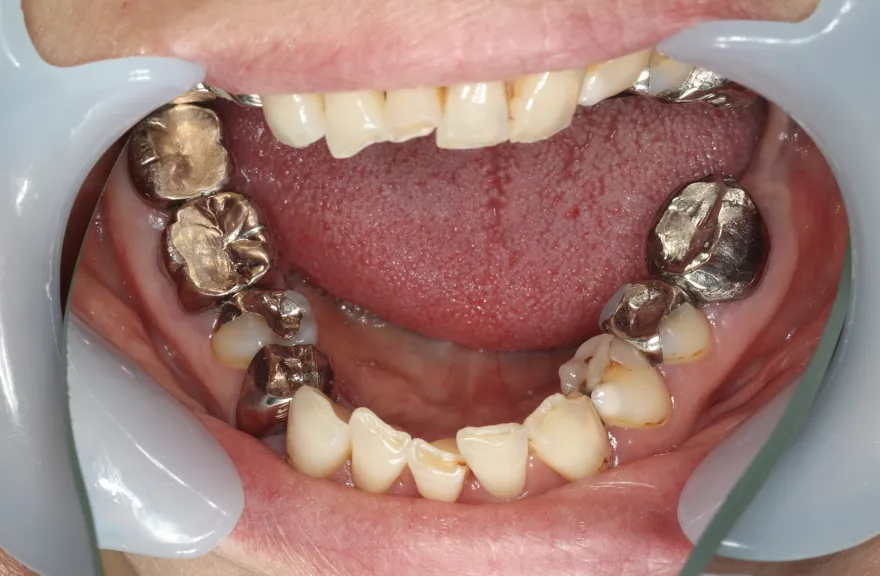

今まで何回歯を入れてもトラブルが起きるために、奥の歯を入れないまま今日に至る、ということでした。

噛み合わせ・骨格を読み解き、今後の人生でトラブルが起きにくいように全体的な治療計画を練りました。 - 治療費用・方針

骨格の前後的な差がある方でした。術前のレントゲンより、上下で歯牙の損傷に明らかな差があるのがみてとれます。

上の歯がないところにインプラント治療を行い、上顎は全てインプラントフィクスチャーによる固定性の歯を入れられることも費用的には可能な方でした。

しかし、治療において重要なのは今目の前の歯を見ることではなく、なぜ目の前の歯になったかを考え、未来へ活かすことです。

骨格的な前後差を考慮することなく歯をいれても、装着した人工物は決して長持ちしません。

今回の症例では、敢えて上顎は総義歯形態をとり、骨格的な前後の差を解消するよう工夫しました。

上顎の残っていた歯も、差し歯としては使えずとも、敢えて根だけ残すことによって組織を温存し、義歯の安定に寄与するよう設計しました。

ここまで全体的にしっかり治療しておけば、今後の人生においてトラブルになるようなことにはならないでしょう。 - 治療のリスク